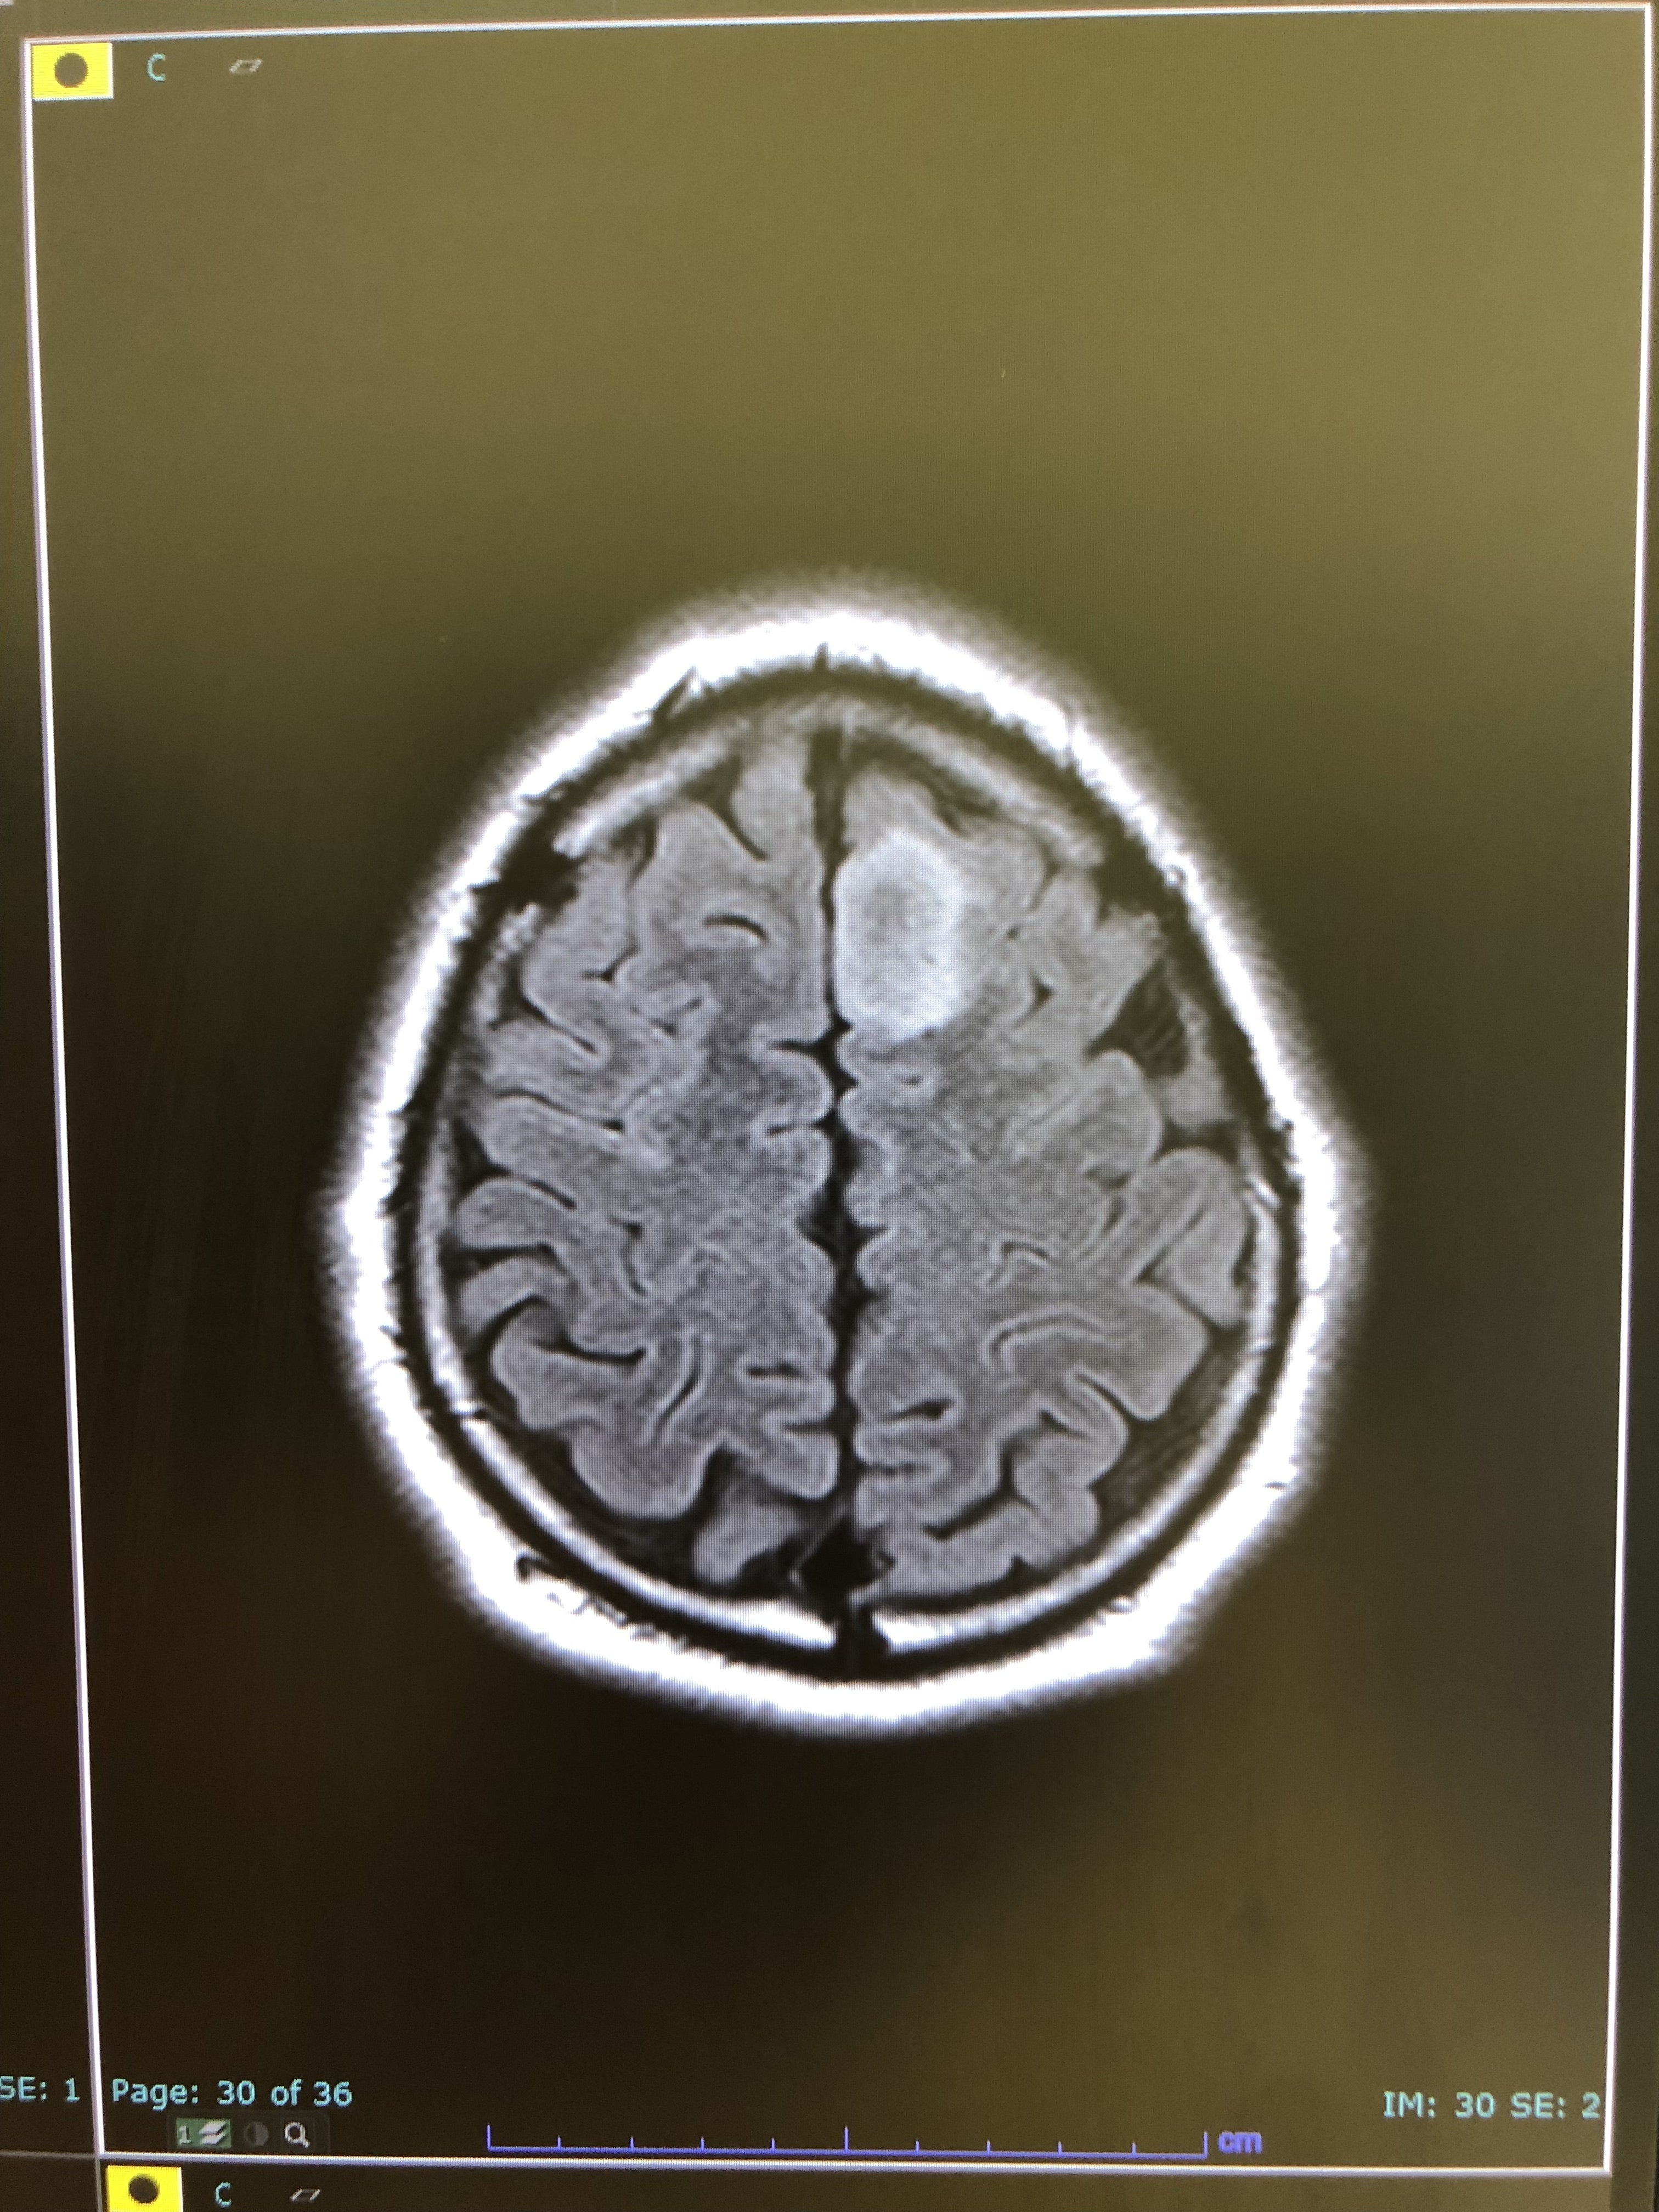

すぐに近くの病院へ行き、MRIを撮ると…

素人目でも「ん?なにかあるな?」と分かりますよね…